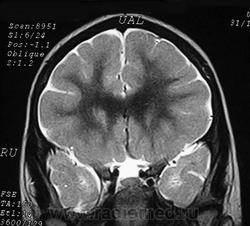

Пахигирия— уменьшение числа вторичных извилин. В пораженном полушарии нервные клетки образуют толстый недифференцированный слой с неправильно расположенными нервными волокнами и группами гетеротопных клеток. Нервные клетки незрелые. Белое вещество истончено. При этом нередко аномально развит корково-спинномозговой путь. Пахигирия может быть односторонней или двусторонней. Генерализованная пахигирия часто наблюдается при микроцефалии.